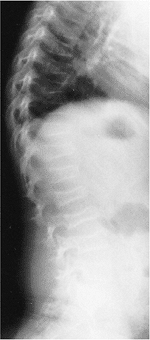

![]() |

Figure 20.18 Thoracic Scheuermann kyphosis. A: Preoperative lateral radiograph. B: Stress lateral radiograph. C and D: Postoperative status of posterior instrumentation and fusion with pedicle screws. (Courtesy of Dr. Anant Kumar.)